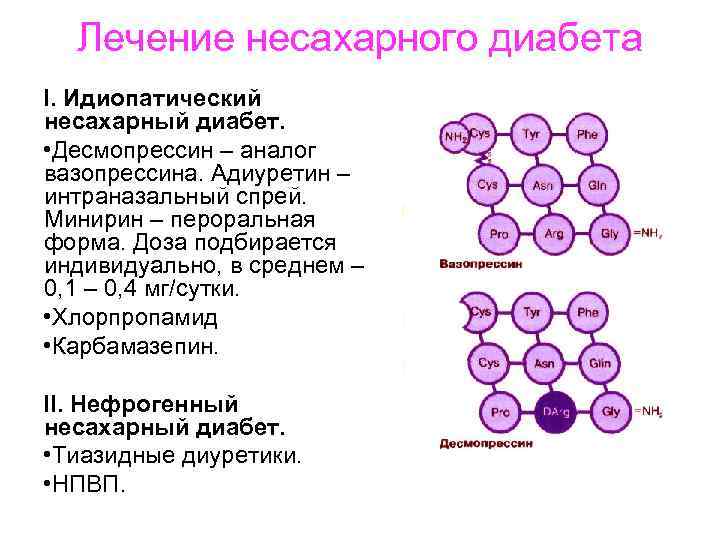

Лечение несахарного диабета I. Идиопатический несахарный диабет. • Десмопрессин – аналог вазопрессина. Адиуретин – интраназальный спрей. Минирин – пероральная форма. Доза подбирается индивидуально, в среднем – 0, 1 – 0, 4 мг/сутки. • Хлорпропамид • Карбамазепин. II. Нефрогенный несахарный диабет. • Тиазидные диуретики. • НПВП.

Лечение несахарного диабета I. Идиопатический несахарный диабет. • Десмопрессин – аналог вазопрессина. Адиуретин – интраназальный спрей. Минирин – пероральная форма. Доза подбирается индивидуально, в среднем – 0, 1 – 0, 4 мг/сутки. • Хлорпропамид • Карбамазепин. II. Нефрогенный несахарный диабет. • Тиазидные диуретики. • НПВП.